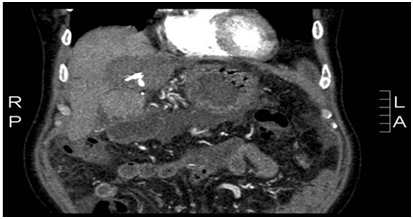

A few years ago 64-year-old Egyptian male was admitted to our gastro-enterology department because of fever. He is known with HCV and hepatocellular carcinoma for which he was operated on in 2008. This operation enhanced a partial left liver resection, but revealed to be irradical. He received RFA additionally (Figure 1). Now he presented himself with ongoing fever, antibiotics had no effect.

Figure 1 After surgery + RFA.

Laboratory showed elevated liverenzyms, especially cholestatic enzymes (AF en GGT) and elevated alpha-fetoprotein. Ultrasound en X-rays showed no abnormalities. During his stay in the hospital he deteriorates and developed ascites. And additional CT scan revealed a portal vein thrombosis (Figure 2). We could not find any other explanation for his complaints than recidive tumor with fever due to tumor necrosis. He was discharged from the hospital after 2 weeks and would be followed up on the outpatient clinic. He should receive palliative chemotherapy. Than in the outpatient clinic the serology of strongyloides and schistosomiasis became positive. The schistosomiasis infection is chronic. He was treated for the strongyloides infection with Ivermectine (one dose) and remarkably his liverenzyms normalized. The ascites disappeared and he had no fever anymore. Also the alpha-fetoprotein deteriorated. The tumor was not progressive for a few years without any therapy.

Figure 2 Portal vein thrombosis.